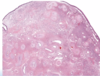

What are the unique histologic features of nasopharyngeal angiofibroma?

Vascular fibrous core lined by benign epithelium

SIMILAR TO spongiosum of erectile tissue